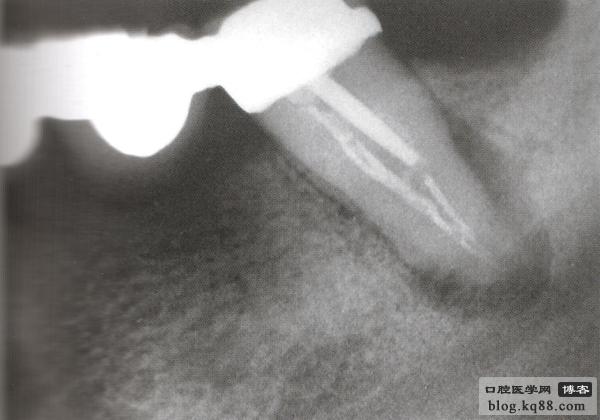

病例2 修復(fù)后根尖出現(xiàn)炎癥冠上開孔再治療

修復(fù)后出現(xiàn)根尖周炎 去除原根充物后試主尖